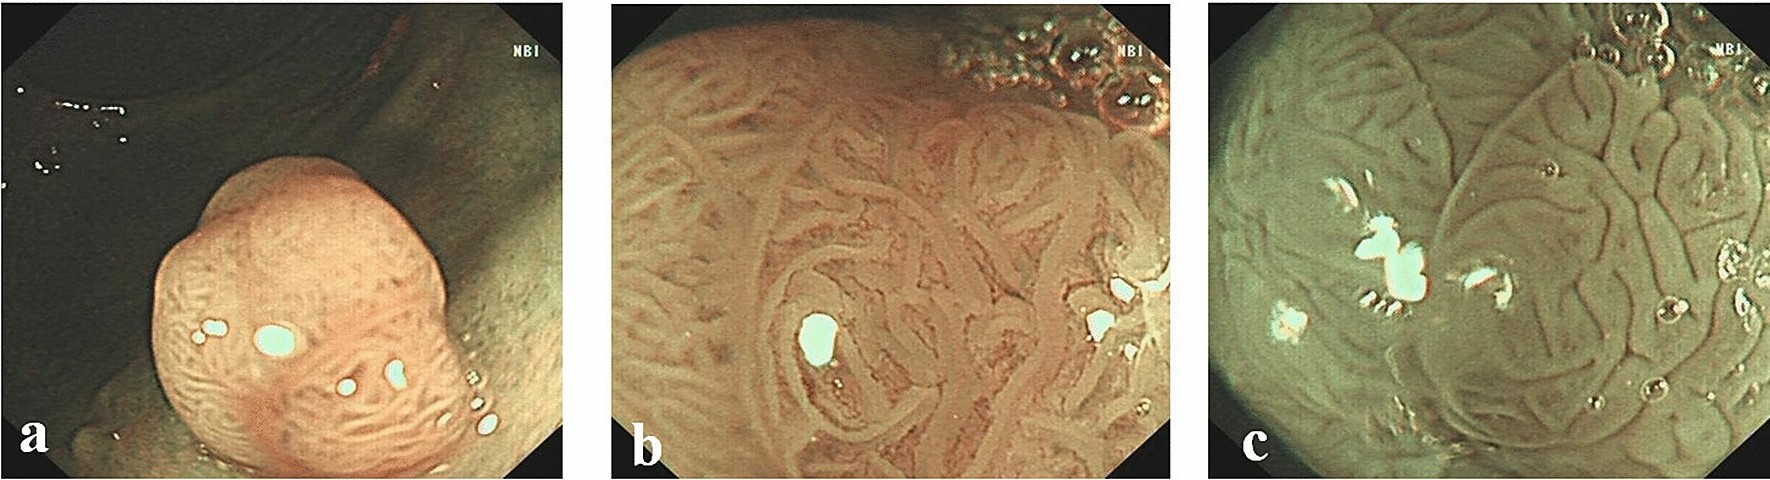

Surface patterns of neoplastic polyps viewed by different modalities: (a) NBI; (b) NBIME; (c) AA-NBIME.